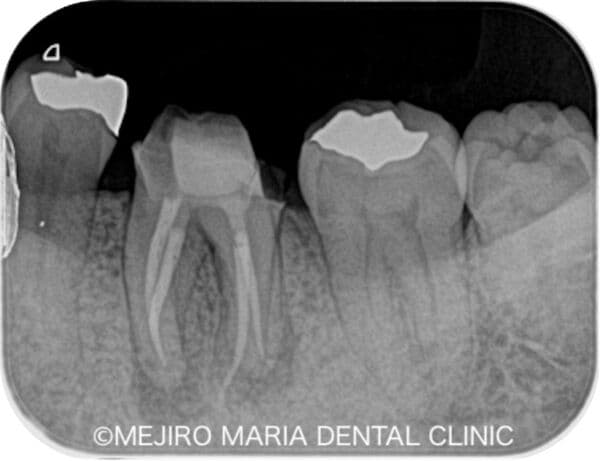

レントゲンの画像

歯髄が不可逆性歯髄炎なのか、可逆性歯髄炎なのかを確実に診断するためには組織切片のサンプルが必要になるため、事実上不可能です。そのため、歯髄の診断では冷たいものや温かいものなどに対する歯髄の反応を見極めることが重要になります。レントゲン、触診、温度診などの診査結果を総合的に踏まえて、現在の歯髄の状況を診断するためには、十分に診査時間を確保することが必要になります。

歯の神経(歯髄)に細菌の感染が広がる